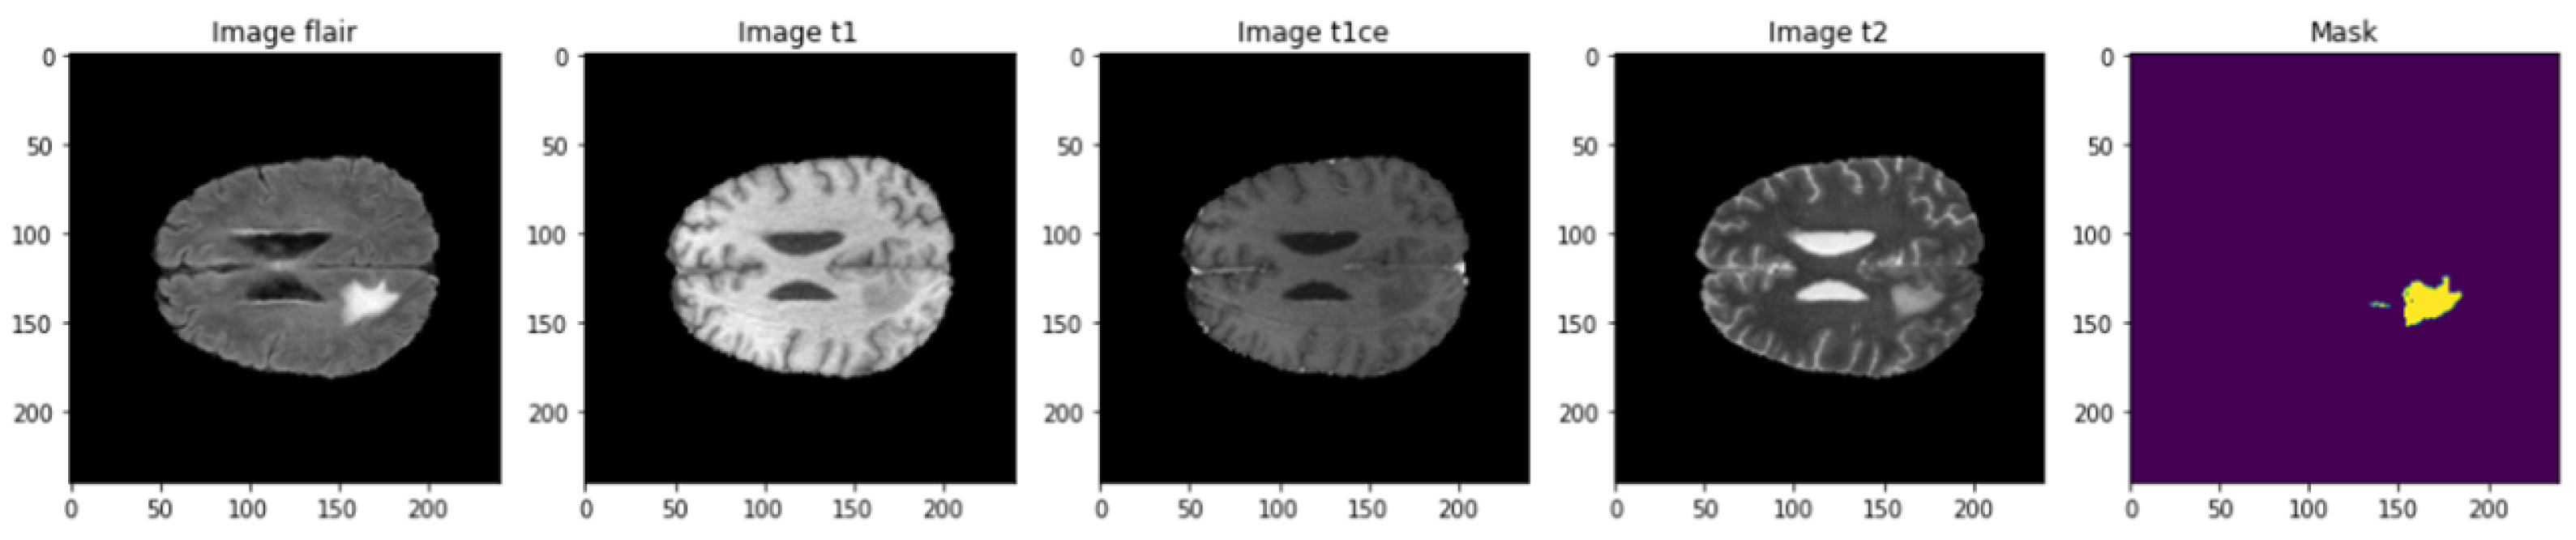

4.1. Dataset Description

4.4. 3D U-Net Segmentation Model